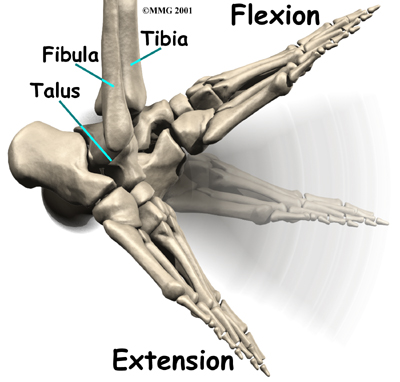

The ankle joint is made up of three bones: the lower end of the tibia (shinbone), the fibula (the small bone of the lower leg), and the talus (the bone that fits into the socket formed by the tibia and fibula).

The talus sits on top of the calcaneus (the heelbone). The talus moves mainly in one direction. It works like a hinge to allow your foot to move up and down.